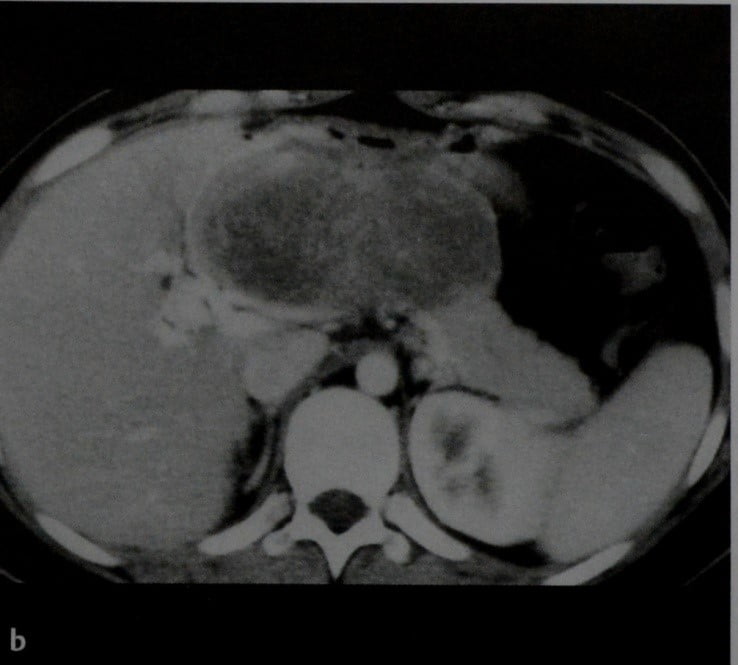

Фотографии и снимки КТ легких без контрастных веществ

Раздел: Визуальный дайджест